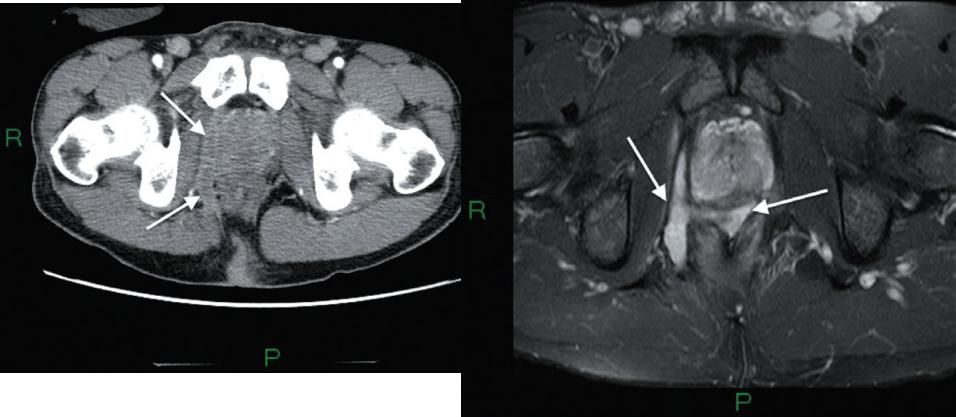

Болезнь Крона:

абсцессы брюшной полости,

перфорация толстой кишки,